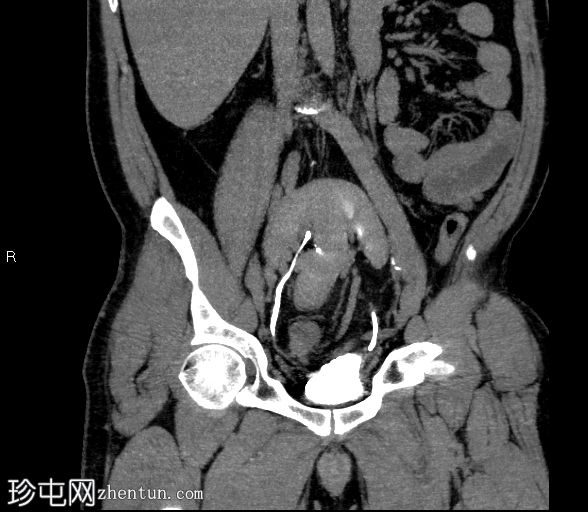

冠状位肾盂排泄期

双肾上极和下极融合,形成扁平肾,在轴位、冠状位和三维图像上均可见。

有两条独立的输尿管,左右输尿管分别独立引流至膀胱。

未见结石或反流压力改变。

本病例展示了扁平肾,这是一种解剖变异,其特征是双肾上极和下极完全融合。这与马蹄肾不同,马蹄肾仅下极通过峡部连接。

虽然扁平肾可能是一种偶然发现,但评估是否存在相关并发症(如肾结石和反复

泌尿

道感染)非常重要。